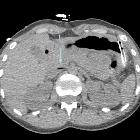

Systemic air

embolism and decompression illnes in a scuba diver.. Arrow shows gas bubbles in some portal branches for the left hepatic lobe.